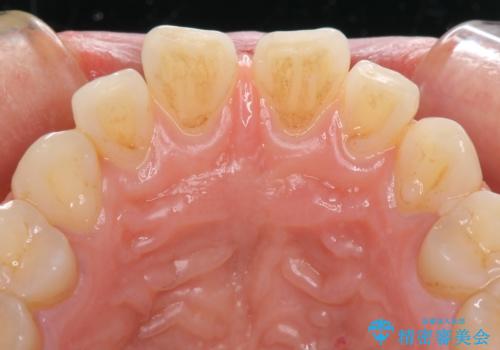

- 上の前歯の隙間を気にして来院された患者様です。

矯正治療により前歯を閉じるという治療を第一選択肢として提案しましたが、期間と費用からオールセラミッククラウンによる補綴治療を行うこととしました。

虫歯もない前歯を削ることは、処置をする者として心苦しいのですが、患者様は矯正治療は選択しないとのことだったので、オールセラミッククラウンにて補綴治療を行いました。